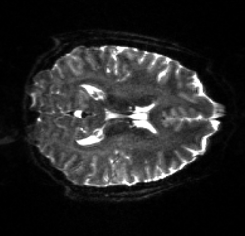

Figure 6: Example field maps (Subject ID 826353) at initialization (top row) and after optimization with Gauss-Newton (bottom row). The first column uses the proposed optimal transport initialization scheme. The middle column uses the same scheme with an additional Gaussian blur to promote smoothness. The right column uses the coarse-to-fine multilevel initialization scheme from HySCO with five levels, and the final field map is optimized at the original image resolution. The multilevel initialized field map is smooth by construction and further optimized to improve the relative image distance at the full resolution. The optimal transport initialization accurately corrects the distortions but is not smooth in the non-distortion dimensions unless blurred with a Gaussian. After the fine-level optimization all field maps are visually similar.

Table 6 reports the runtime and correction quality for PyHySCO using GN-PCG, HySCO, and TOPUP. On real 3T and 7T data, PyHySCO achieves lower loss and higher relative improvement between corrected images than HySCO, and higher relative improvement than TOPUP. The runtime on CPU for real data is 1-2 minutes for HySCO and over 1 hour for TOPUP, while PyHySCO on GPU has runtimes of 10-13 seconds. For the simulated dataset, PyHySCO requires an average of 1 minute on GPU, HySCO an average of 12.6 minutes on CPU, and TOPUP an average of 8.5 hours on CPU. Using the ground truth field maps from the simulated dataset, PyHySCO achieves the lowest average field map relative error, 14.48%, compared to 19.70% for HySCO and 16.36% for TOPUP. Figures 7, 8, and 9 show the field map and corrected images for one example subject from each dataset. The results of the methods are similar, and the resulting field maps are comparable to those of the existing tools, HySCO and TOPUP, while PyHySCO is considerably faster.